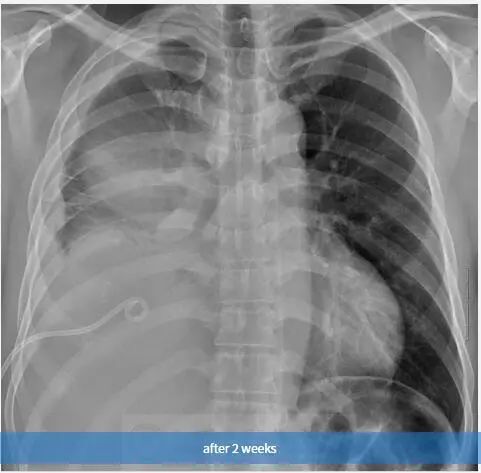

图3 2周后,随访胸片示右胸弥漫性阴影和胸腔积液。也可见引流管。